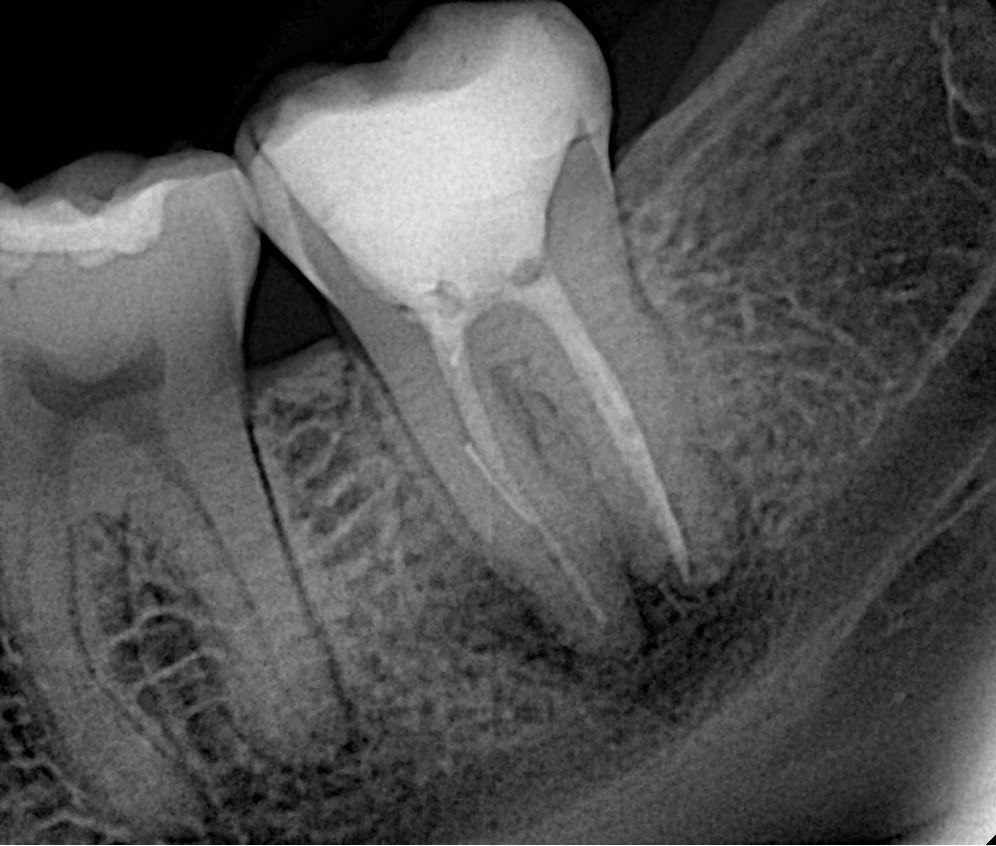

Retratamento Endodôntico

Em algumas situações é necessária a reintervenção endodôntica, ou seja, é preciso realizar um novo tratamento de canal.